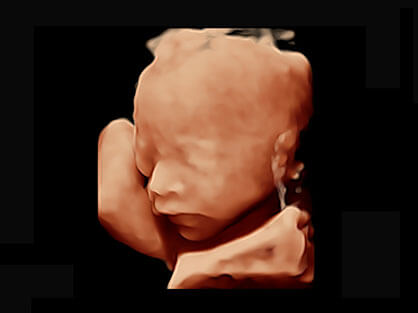

• M-Slice多切面成像

0.5mm厚度的薄层切片显像,可清晰显示微小病灶的连续断面。

• S-Live Silhouette光影成像

可同时显示组织结构表面和内部的轮廓信息,达到透视效果,为临床提供更丰富的诊断信息。